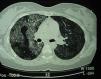

Pulmonary alveolar proteinosis (PAP) is a rare disease that was first described in 1958.1 It is characterized by the accumulation of surfactant-like lipoproteinaceous material in the distal air spaces and terminal bronchi, which may lead to impaired gas exchange2 (Fig. 1). This accumulation of surfactant is due to reduced clearance by the alveolar macrophages, and another feature of the disease is the presence of phospholipoproteic material within the alveolar macrophages. Estimated yearly incidence is 0.2–0.4cases/million, and prevalence is 3.7–6.2persons/year.3 As of 2002, around 410 cases had been described in the literature.4